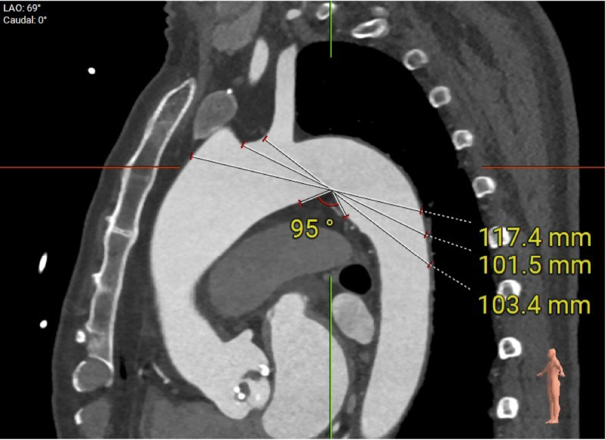

此患者解剖结构复杂:1)升主动脉明显增宽,平均直径达到54.5mm。

该结构需谨慎评估血管夹层和破裂风险,对瓣膜系统的通过性能要求极高。

2)患者主动脉根部结构复杂,为Type 2型二叶瓣畸形,左右对合缘、右无对合缘处均可见钙化融合嵴,瓣环平面可见严重钙化,左冠窦底钙化灶延伸至左室流出道,且左室腔小。